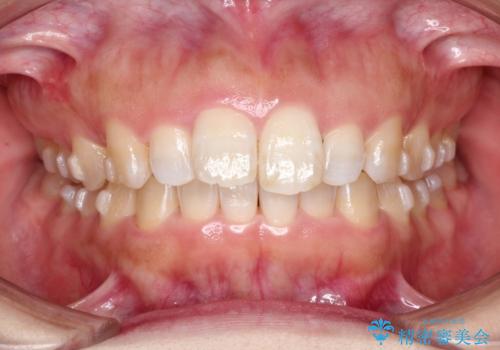

【出っ歯が気になる】インビザライン症例

- 前歯の歯並びの改善を希望され来院された患者様です。

初診時の歯並びの状態としては、上の前歯が下に対して前に飛び出た上顎前突という状態で、前歯は大きく前に飛び出した状態により患者様も口の閉じづらさを感じているとのことでした。また上顎に軽度の叢生(ガタガタ)がありました。

抜歯は行わず上顎の奥のスペースを利用して歯をスライドする方法の他に歯列弓の拡大やディスキング(歯と歯の間の隙間を作る処置)を行い叢生を改善しました。

奥歯を後ろに送る工程では上下でゴムかけをしていただきました。

矯正装置としてはマウスピースを使用しています。

見た目、嚙み合わせ及び、治療期間や施術内容に大変ご満足いただきました。